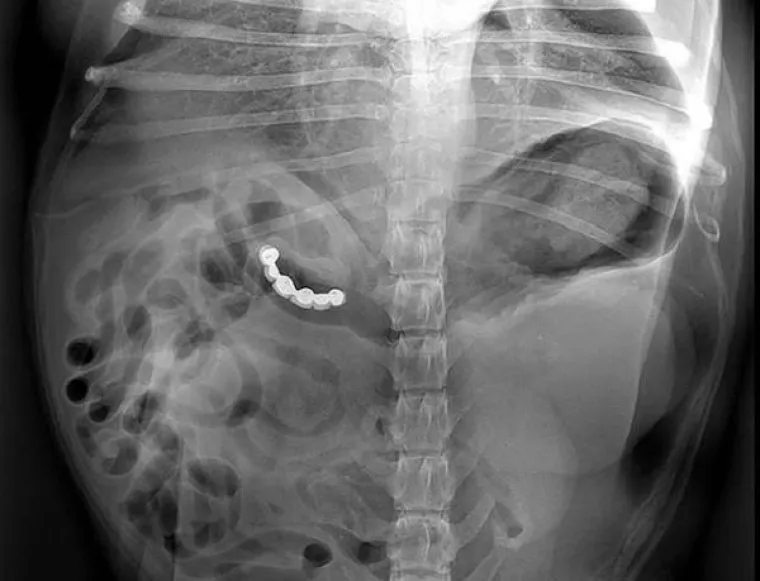

LJUDI SU ČAROBNO SPREMIŠTE, U NJIH STANE BAŠ SVE: Nevjerojatne snimke pokazuju što su sve uspjeli ugurati u sebe